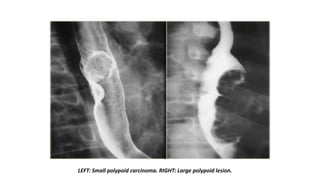

LEFT: Small polypoid carcinoma. RIGHT: Large polypoid lesion.

LEFT: Small polypoidcarcinoma. RIGHT: Large polypoid lesion.